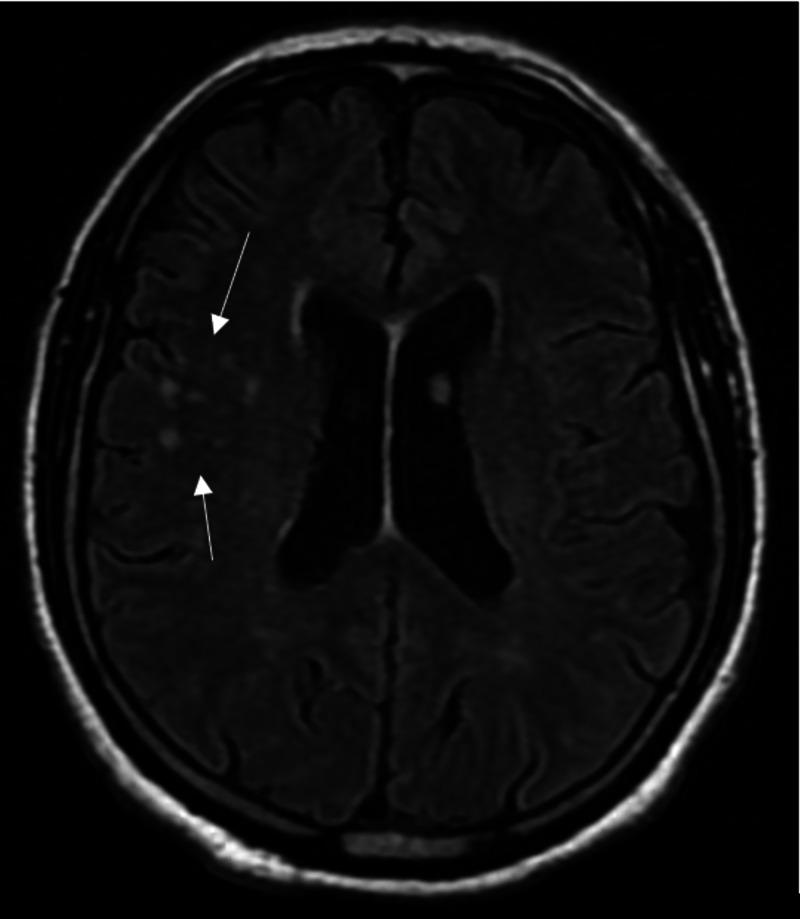

Cryptococcosis is a fungal infection that mostly affects immunocompromised patients. Diagnosis is based on the detection of cryptococcal antigen in the cerebrospinal fluid (CSF) or serum. Antifungal resistance is emerging, making treatment difficult and long. We report a case of cryptococcosis in a patient with multiple myeloma, years after undergoing a bone marrow transplant. Symptoms were mild, and imaging studies were nonspecific. CSF analysis revealed positive cryptococcal antigen. The patient was started on the standard three-phase antifungal therapy and recovered.

隐球菌病是一种真菌感染,主要影响免疫功能低下的患者。诊断基于脑脊液(CSF)或血清中隐球菌抗原的检测。抗真菌耐药性正在出现,使得治疗困难且疗程漫长。我们报告一例多发性骨髓瘤患者在接受骨髓移植数年之后发生隐球菌病的病例。症状较轻,影像学检查无特异性。脑脊液分析显示隐球菌抗原阳性。该患者开始接受标准的三相抗真菌治疗并康复。